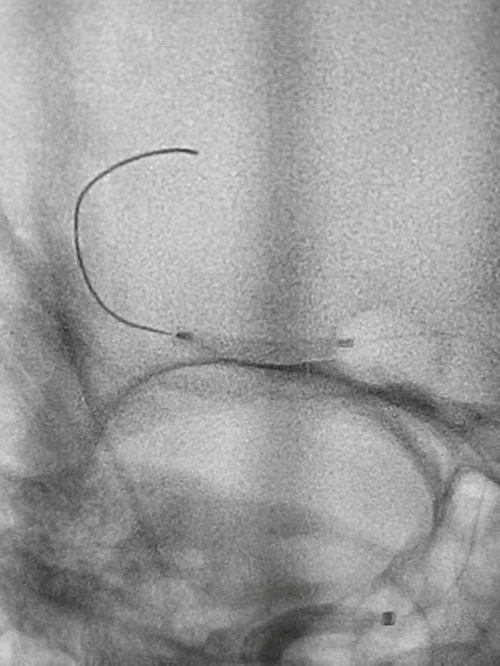

时间就是生命,提高一秒就多一分胜算。15分钟后,手术团队一切准备就绪,将病人接到手术室,他们立即给予宋大爷全脑血管造影+血管闭塞开通术。经过抽吸和支架辅助取栓,医护团队取出了大约10毫米×1毫米的血性斑块,闭塞血管顺利开通,远端血管恢复显影。术中进一步探查发现,宋大爷大脑中动脉主干存在严重狭窄,李首春副主任医师随即实施球囊扩张+血管内支架植入成形术,彻底改善血管狭窄问题。从术前准备到手术结束,整个过程仅用时1小时。术后3天,宋大爷意识清晰,语言功能恢复流利,右侧手脚活动自如;术后第4天,他已能独立步行,顺利康复出院。